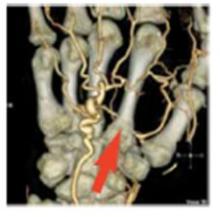

OrthoWorks ProPlanner is a soon-to-be-released workstation or customizable plug-in clinical application available to OEM companies and healthcare professionals for orthopedic support on existing PACS and RIS/PACS systems. Designed for rapid implementation, it provides a means for OEM companies to upgrade current customer bases and expand into new revenue opportunities.

Extending beyond basic orthopedic planning, the workstation provides support for deformity corrections, trauma and customized planning methodologies that mimic orthopedic workflow.